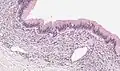

| Micrograph showing a mucinous cystadenoma of the ovary. H&E stain. | |

Mucinous cystadenoma is a benign cystic tumor lined by a mucinous epithelium. It is a type of cystic adenoma (cystadenoma).